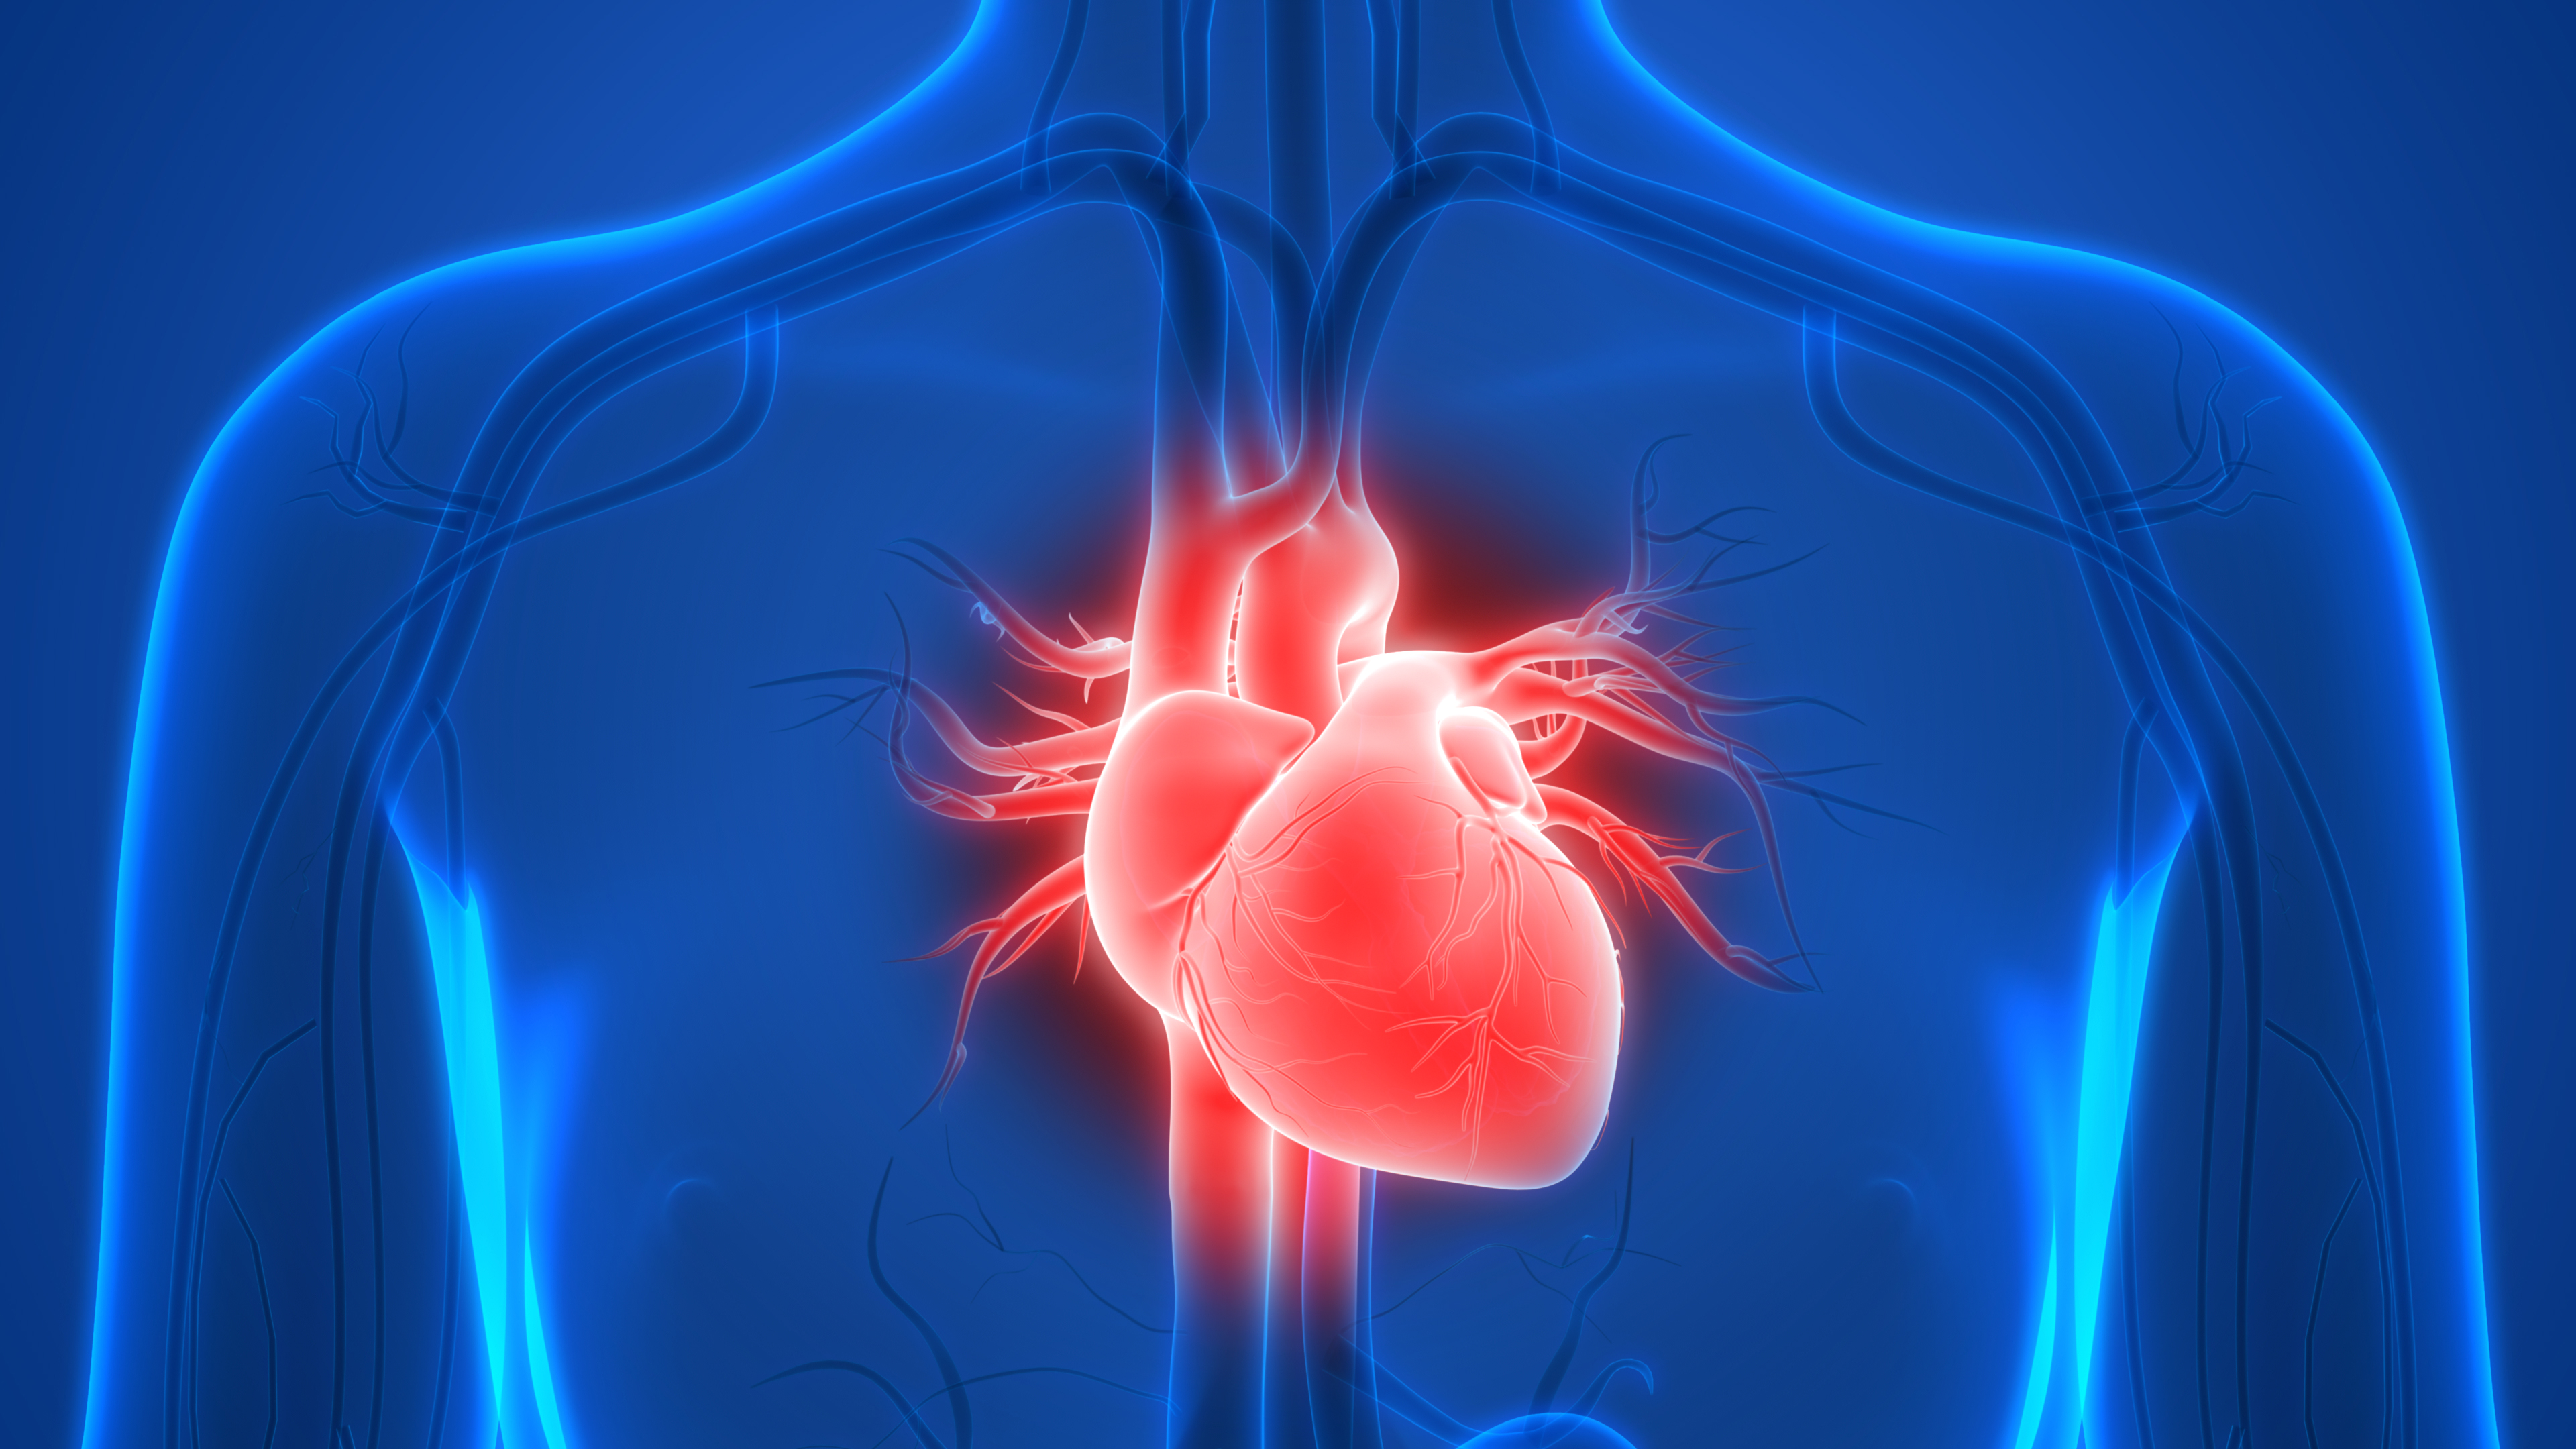

Анатомия здорового сердца: фотографии и иллюстрации